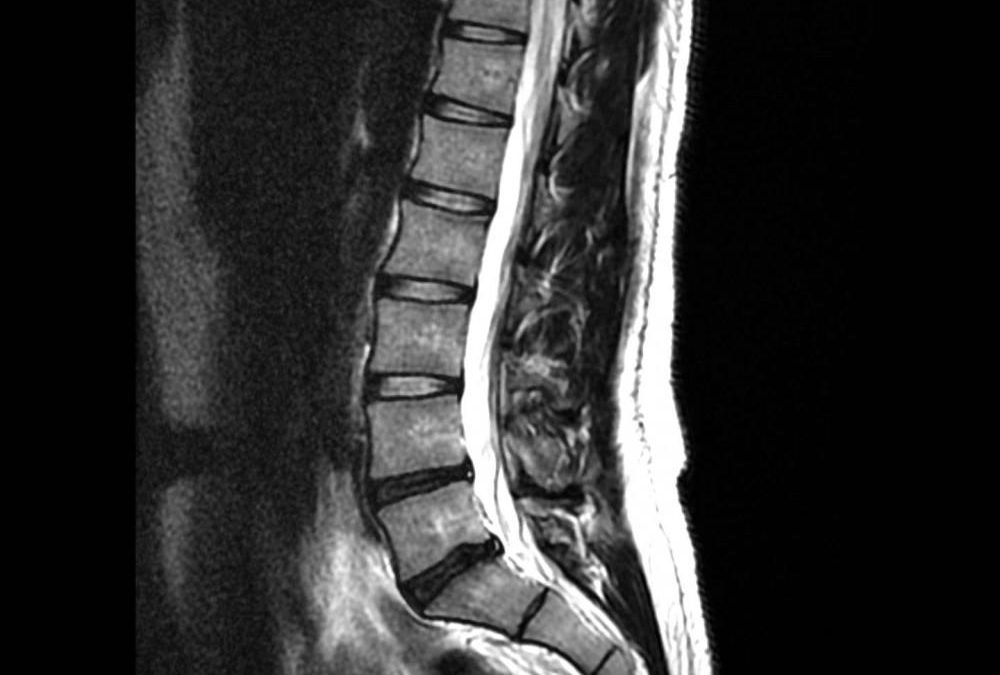

The Ontario government recently announced that they will begin consultations on a proposal to allow chiropractors to order advanced imaging like MRI, CT scans and diagnostic ultrasound. This exciting development will enhance patient care by streamlining the imaging process and help patients get the care they need sooner. Chiropractors are ideally suited to identify when these important tools are needed, and patients agree! A recent IPSOS poll of Ontarians found that an overwhelming majority of chiropractic patients – 97 per cent – support chiropractors being authorized to order these valuable tests. Now that the government has also acknowledged the value of enhancing chiropractors’ scope of practice, we invite our patients to make sure that these consultations leave the government with a clear mandate: grant chiropractors the authority to order MRIs, CT scans and ultrasounds. Click on the link below to have your voice heard!